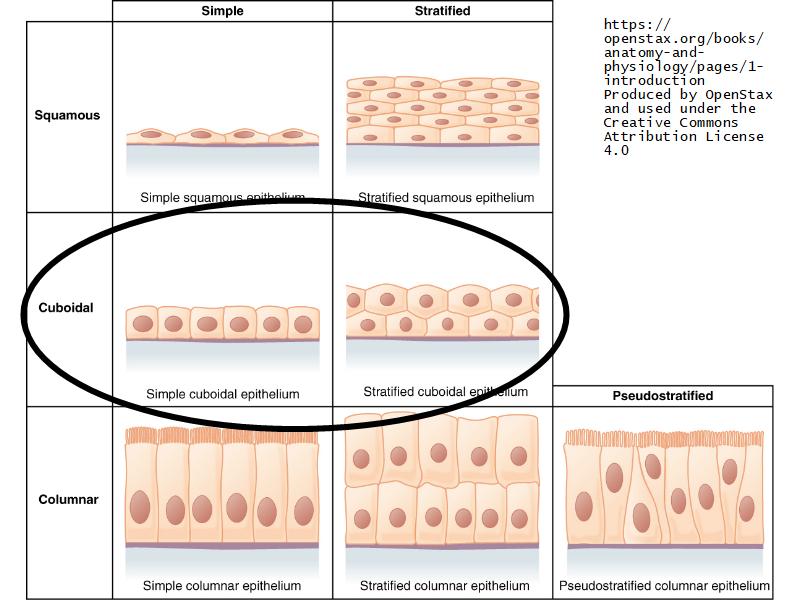

Mammary gland

Write short notes describing the structure of the mammary gland.

(5)

Mammary gland

- Compound tubuloalveolar gland

- 12 - 20 glands

- Each with own lactiferous duct

- Each with own lactiferous sinus

- Opens on skin at apex of nipple

Structures

List the structures and cells found in the mammary gland.

Structures

- Lactiferous sinuses

- Stratified squamous near opening on skin

- Stratified cuboidal other parts

- Lactiferous ducts

- Stratified cuboidal

- Myoepithelial cells

- Underlie lactiferous ducts in most areas

- Basal lamina

- Separate epithelial components from stroma

What are the main morphological features of the nipple?

(4)

Morphology

- Covered with skin

- Consists of dense collagenous connective tissue

- Interlaced with smooth muscle fibres

- Contains openings of lactiferous ducts

Skin

- Keratinized stratified squamous epithelium

- Sebaceous glands

Stroma

- Collagenous connective tissue

- Irregular dense connective tissue

- Smooth muscle

- Fibres and bundles

- Lactiferous sinusses

- Stratified cuboidal epithelium